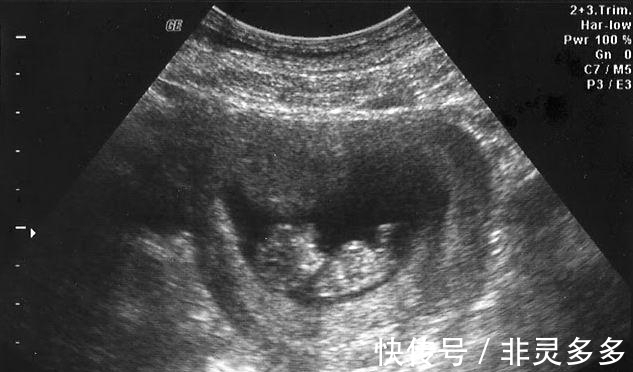

朱妈妈提到,当时刚好星期日,完全没有妇产科有开,便想说那就等隔天再看好了,可是大姐很坚持要她立刻马上去挂急诊,她只好找老公一起去医院,「在测胎音时,医生说胎儿的心跳很弱,建议现在就要剖腹,我就这样剖腹生了」。最让她印象深刻的是,医生接生到一半,突然转头跟助理说,「是脐带扭转,去拿相机」,拍了张照就继续接生,「等手术结束后,医生拿照片给我看,又把照片拿给家人看。医生说,这是脐带扭转的状况,导致养份没办法送到胎儿身上,若是再慢个1至2天,小孩就没了」。

【 小孩|2岁女娃说我在肚子里玩一条线,,医生:再慢1天小孩就没了】后来,朱妈妈跟女儿在聊天时,突然想到孩子在3岁前是存有胎内记忆的,便随口问了2岁女儿,「你肚子里都在干嘛?」结果妹妹回她,「在玩玩具啊!」,妈妈回,「乱讲,我肚子里哪有玩具?」,殊不知女儿又说,「有啊!有一条线,我一直卷、一直卷~」让她听完瞬间惊呆,这真的就跟她当时在急诊剖腹生的状况一样啊!还好最后孩子有平安生下来……。看到这里,大家应该都更相信胎儿对未出生时的状况是有记忆的吧~有兴趣的话,可以找家中的宝宝来问问看哦!